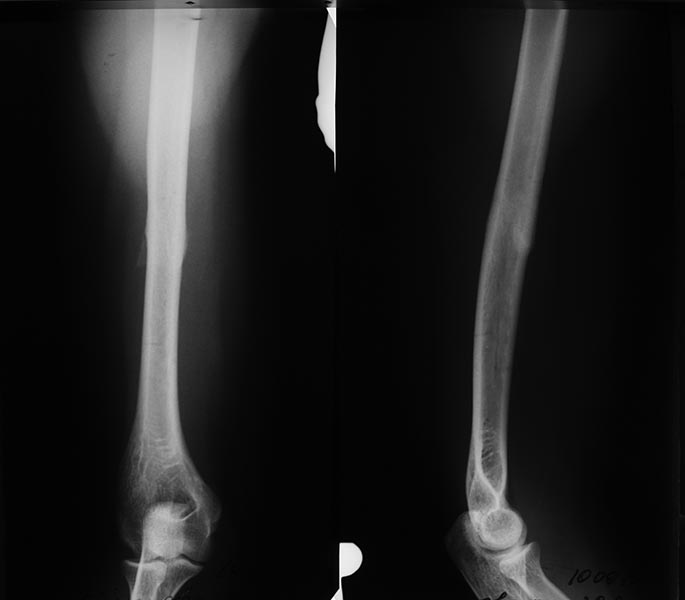

Re: перелом голени

Кто это понял? Первичное сращение - эталон сращения, что для мягких тканей, что для костей. Это аксиома. Не может же природа сделать исключение для последних. В этом вопросе жирная точка поставлена еще в 60-е годы прошлого века. Это фундаментальные работы Краснова, Флоренского, Виноградовой, Лаврищевой,Стецулы, Friedenberg, Ford, Key, Decolux, Razemon и, конечно же, Г.А.Илизарова. В последние годы имеют место неуклюжие попытки пересмотреть данное положение. Это абсолютно несостоятельные и ненаучные потуги, извиняюсь за жесткий тон. Единственный предъявляемый аргумент - непрочность первичного сращения. Однако смотря в каких условиях оно достигнуто. Если в условиях абсолютной или близкой к ней стабильности, например. при накостном остеосинтезе, то оно однозначно непрочное и по сути первичным не является. Это как консолидация в условиях невесомости с образованием остеоподобной, бесструктурной спайки. Кстати, эта проблема хорошо освещена в работах S.Perren. При чрескостном остеосинтезе контактный регенерат формируется в условиях гравитационного напряжения вследствие прогиба спиц и постепенного снижения жесткости фиксации. Это структурно правильно ориентированный и прочный регенерат, т.е. истинное первичное сращение. В этом году у меня не было ни одной рефрактуры. Даже умеренно выраженная периостальная реакция для меня является неудачей, поскольку она является объективным признаком нестабильной фиксации. А так клинико-рентгенологические признаки первичного сращения с полным отсутствием периостальной реакции получаются у каждого 6 пациента. Однако о первичном сращении можно говорить только по результатам морфологического исследования. Отсюда следует, что оно является крайне редким явлением. Не всякое интермедиарное сращение можно расценивать как первичное. Очень интересные работы по данному вопросу у Баскевича.

Вот типичный пример консолидации с минимальной периостальной реакцией.